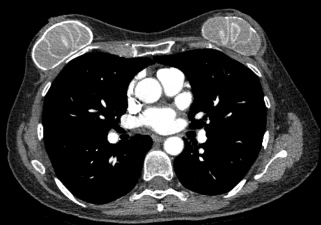

The authors present a unique case where radiographic imaging was misleading due to an undocumented unusual breast augmentation procedure that used multiple small “gnocchi-like” silicone implants.